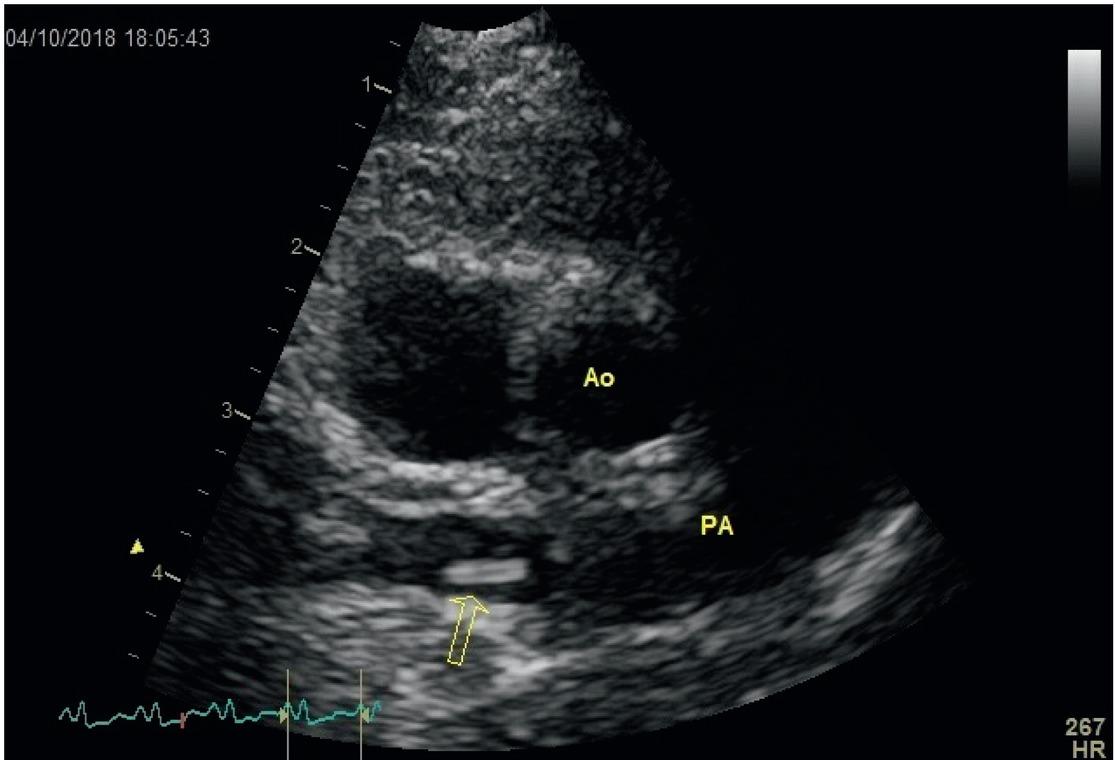

Fig. 2